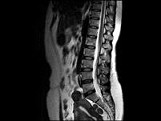

- 单项选择题女,37岁, 下腹部不适,MRI检查如图所示, 下列说法错误的是 ( )

A、子宫底部局部隆起,该病灶边界清晰

B、病灶T

WI信号与子宫肌层的信号相同C、病灶T

WI信号为明显低信号D、此为子宫粘膜下肌瘤

E、此为子宫浆膜下肌瘤